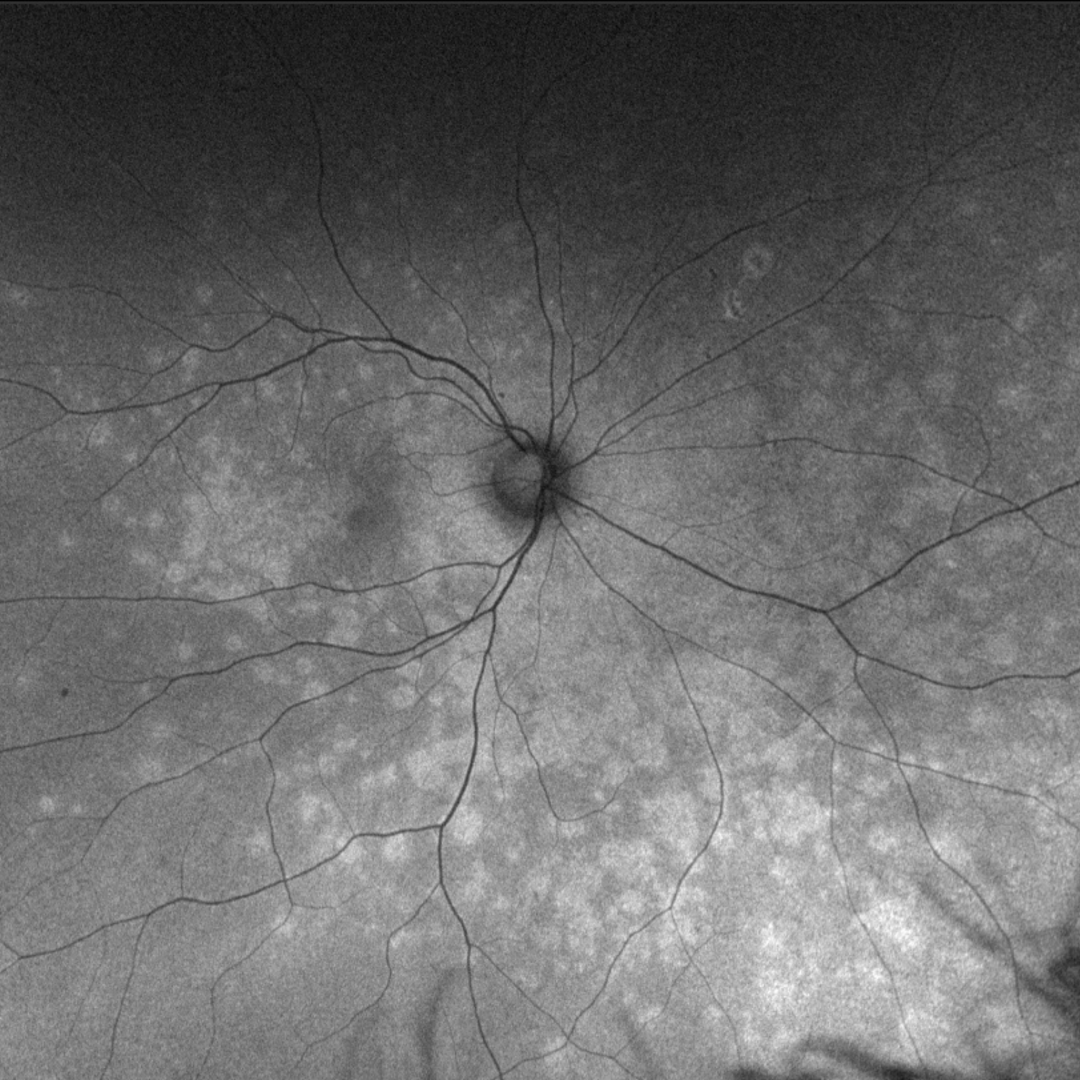

Fundus autofluorescence imaging shows hyper-fluorescence of the white retinal dots and pinpoint hypo-fluorescence in the area of foveal granularity.

More infoFundus autofluorescence image (initial visit - right eye)

More infoFundus autofluorescence image (follow-up visit - right eye)